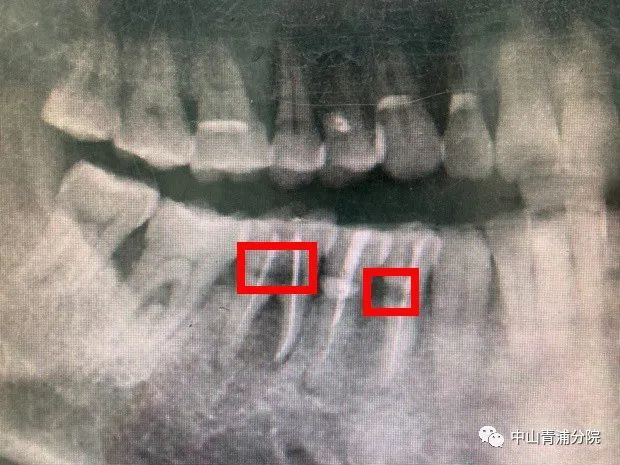

接诊医生进行检查后发现,刘老伯右侧下方第一颗前磨牙,第一颗磨牙颊侧可见深2mm缺损,探诊疼痛,冷测检查疼痛明显,持续近10秒,同时,X线片检查显示:颊侧缺损深至牙髓,伴随牙槽骨轻度吸收(图A)。医生为刘老伯制定了详细的治疗计划,随后为他进行了根管治疗(图B),为刘老伯后续的牙周治疗和修复治疗做准备。